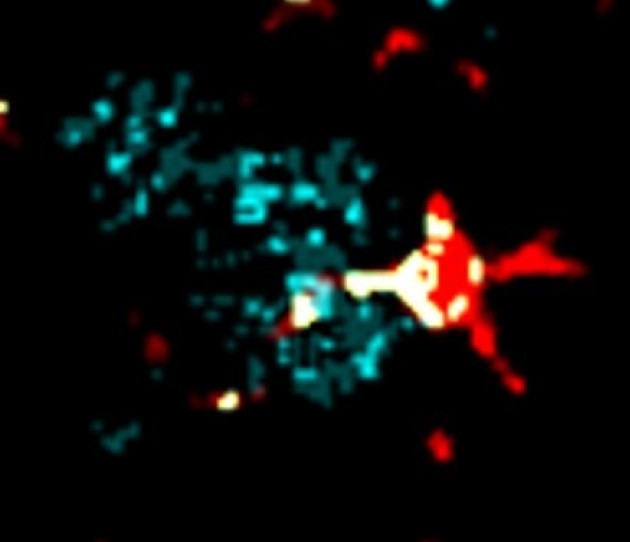

Microglia and Amyloid Plaques - Callum Muirhead and the Multi-Omics Atlas Project team

"Imaging mass cytometry image of amyloid plaques (red) and microglia (cyan)."

"Co-localization of amyloid plaques and microglia (white)."